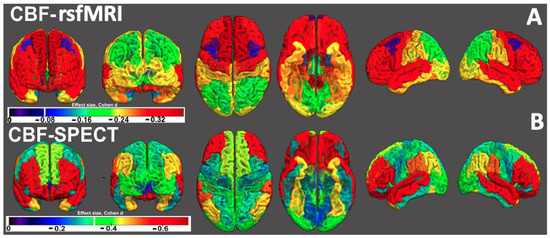

3.2. rCBF Differences Between the UKBB MDD Cohort and the Amen Clinics Inc. Cohort